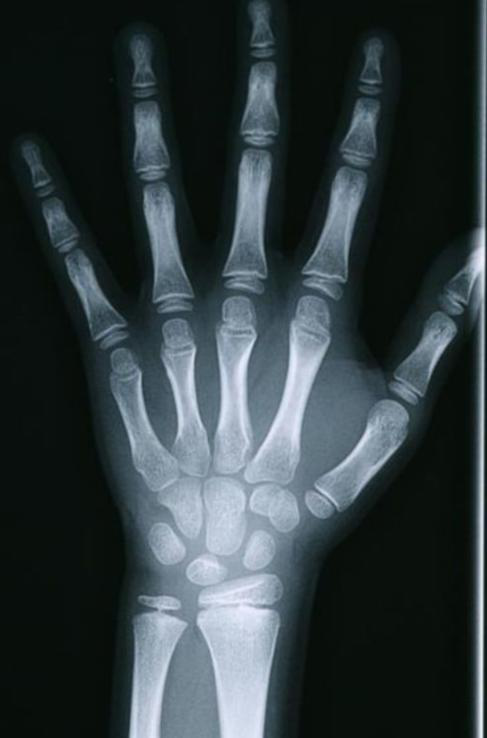

骨龄是指骨骼发育的年龄,是儿童骨骼成熟度的一种测量标准。通常通过拍摄左手腕部X光片,通过X光片观察骨化中心出现的时间、数目、形态变化及其融合时间,判断骨骼实际发育程度,来确定生物学年龄。 2.骨龄评价有何意义? 骨龄的评估,有助于了解儿童生长发育程度及性成熟的趋势,了解儿童身高发育的潜能,也可以大概预测儿童的成年身高,还可以辅助诊断某些小儿内分泌疾病。 3.骨龄如何监测及评估? 生物年龄(骨龄)-生活年龄的差值在±1岁以内的称为发育正常。 生物年龄(骨龄)-生活年龄的差值>1岁的称为发育提前(简称:早熟)。 生物年龄(骨龄)-生活年龄的差值<-1岁的称为发育落后(简称:晚熟)。 骨龄发育异常,代表孩子身体的某些方面出现了问题,而且影响了孩子身高的发育。 (性早熟的时候,骨骺提前融合,成年最终身高降低!) 4.骨龄评价有何意义? 导致骨龄提前的因素:性早熟、肾上腺皮质增生症、肿瘤、甲亢、单纯性肥胖等。 导致骨龄落后的因素:生长激素缺乏症、Turner综合征、甲减、软骨发育不全等。 身高停止生长的标志:骨骺闭合。(男童16岁,女童14岁) 骨骺未融合的骨龄图 骨骺融合的骨龄图 5.如何科学管理身高? 1. 到正规医院的儿童内分泌科就诊。 2. 骨龄测定。 3. 合理饮食,营养均衡。建议每天300~500ml的牛奶,1个鸡蛋,适量的各种肉类、谷类及水果蔬菜,同时注意科学补充维生素D。不建议吃营养滋补品,如海马、田七、燕窝、人参、蜂皇浆、牛初乳、滋补中药材等。 4. 充足的睡眠。生长激素在深度睡眠1小时左右分泌最旺盛,夜间分泌较白天多,建议最迟晚上10点前入睡。 5. 科学的运动。多进行跳绳、打篮球、羽毛球、游泳、跑步等拉伸的体育运动可促进长高。每次运动心率不超过140次/分。 6. 愉悦的心情。尽量多发掘孩子的闪光点进行夸赞,餐桌上、入睡前不打骂孩子,轻松愉快的情绪可促进生长激素分泌。 温馨提示 阳春市妇幼保健院身高管理、骨龄检查时间: 周二、周六全天 预约方式: 关注“广东省阳春市妇幼保健院”微信公众号 选择小儿内分泌专科预约挂号